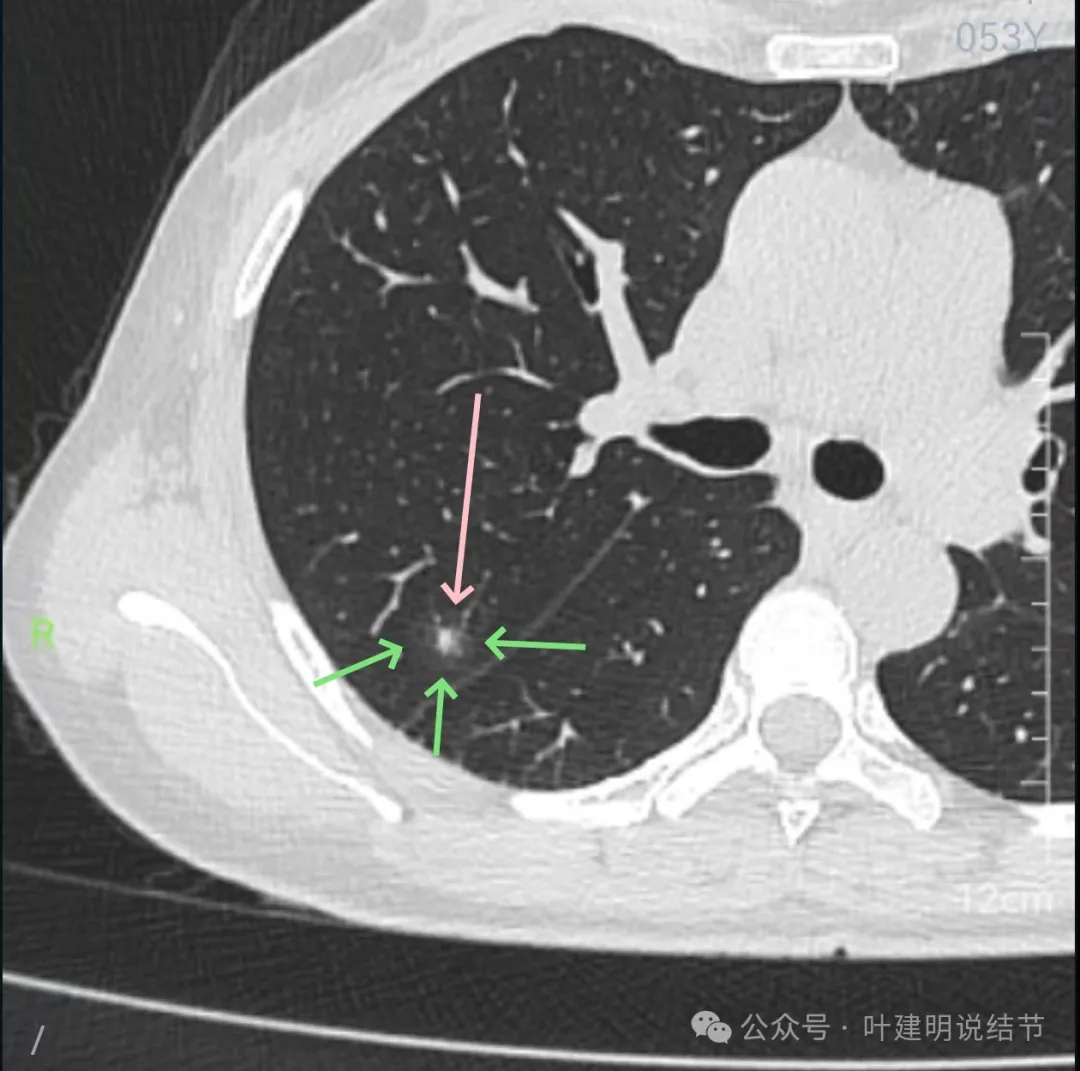

先来看2024年10月16日的影像:

右上后段混合密度结节,瘤肺边界欠清,有明显实性成分,边缘不光滑。

右肺很淡的磨玻璃阴影,伴进入的血管异常增粗,整体轮廓尚显清楚。

右下叶背段边界欠清的磨玻璃影,有血管刚好位于病灶处。

病灶出现,轮廓不清,瘤肺边界模糊,有血管穿行,血管有异常增粗。

血管壁有异常密度增高,病灶混合密度,轮廓总体在此层较清,但瘤肺边界不清。

病灶偏实性部分不密实,磨玻璃部分过淡且模糊。

边缘有毛刺,但不够锐利;外周磨玻璃成分密度过淡且界限不清;实性部分也显得不致密;与叶间裂距离近但没有任何牵拉影响。

实性成分在灶内看,也是界限不清,磨玻璃部分淡而糊。

整体感觉像病灶中间偏实性些的成分伴外周晕征。

边缘区域离叶间裂更近,仍无牵拉。

几乎贴着叶间裂了,仍无任何牵拉影响。

病灶密度边缘部分也不均,离叶间裂近而没有影响。

上图病灶已经贴着叶间裂,但仍显示是平直的,没有任何牵拉影响。

矢状位上看,病灶虽整体轮廓较清,但瘤肺边界显模糊,整体不致密。

冠状位上看病灶有实性成分,实性成分缺乏收缩力,外围是淡磨玻璃成分,瘤肺边界欠清,贴着叶裂没有影响。